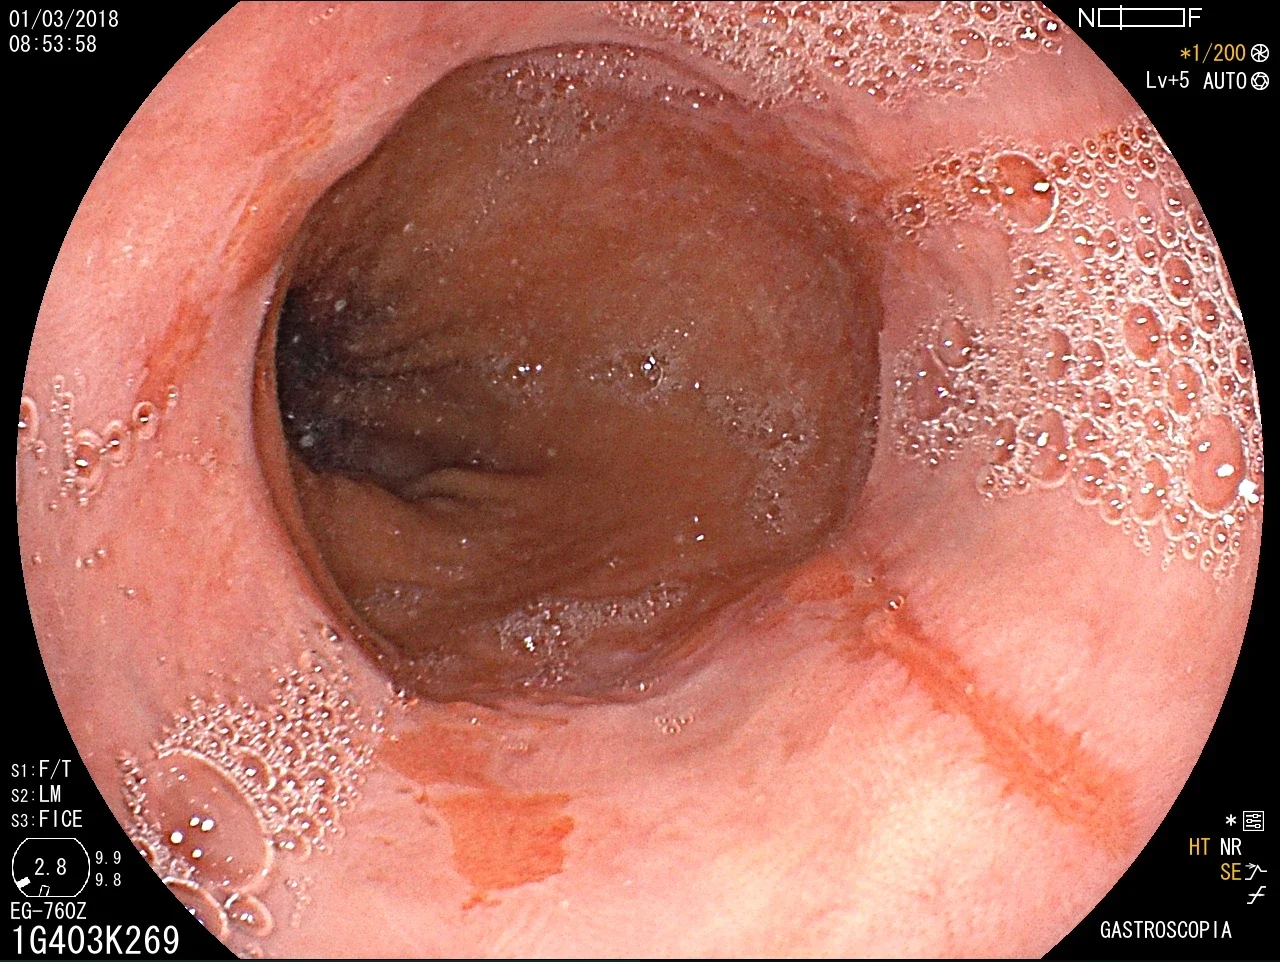

Introducción del gastroscopio bajo visión directa para examinar esófago, estómago y duodeno.